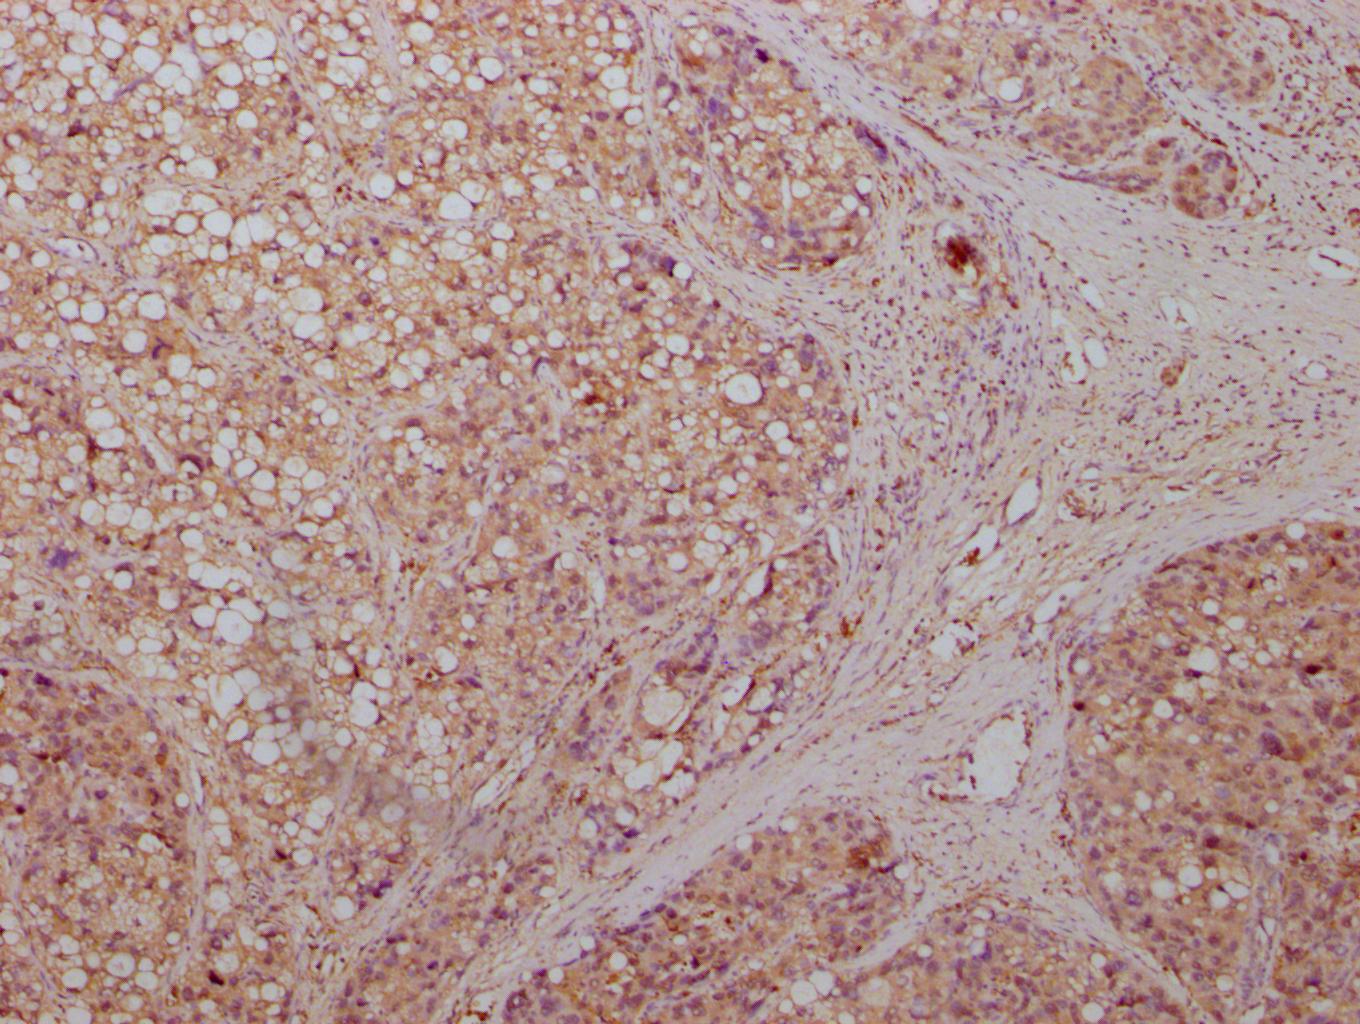

IHC image of CSB-MA007670A0m diluted at 1:500 and staining in paraffin-embedded human liver cancer tissue performed on a Leica BondTM system. After dewaxing and hydration, antigen retrieval was mediated by high pressure in a citrate buffer (pH 6.0). Section was blocked with 10% normal goat serum 30min at RT. Then primary antibody (1% BSA) was incubated at 4°C overnight. The primary is detected by a biotinylated secondary antibody and visualized using an HRP conjugated SP system.